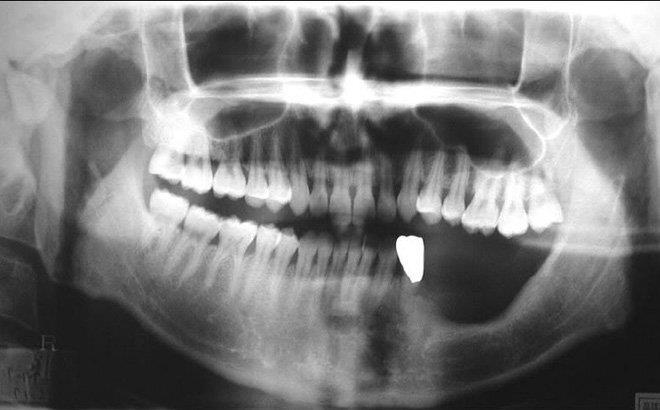

Một nam thanh niên 31 tuổi bị đau răng nhưng ngại đi khám, đến 6 tháng sau khi không chịu được nữa, anh đi khám thì nhận được kết quả vô cùng bất ngờ.